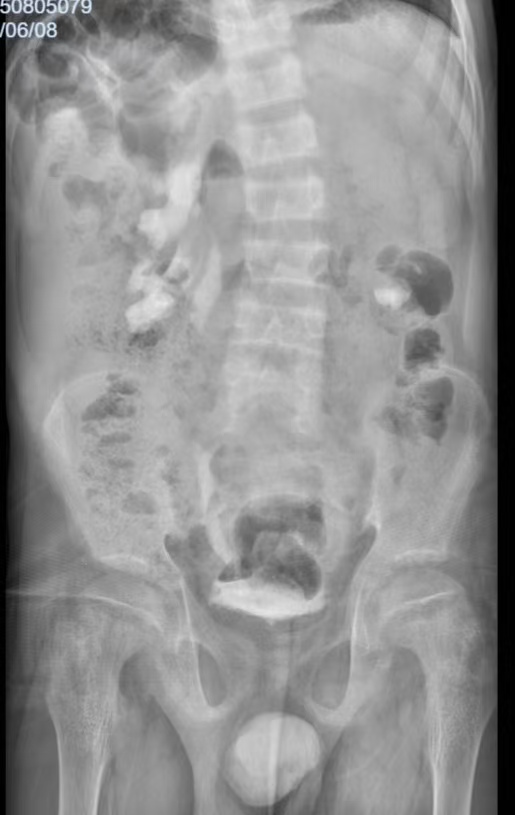

(膀胱造影排泄末期)

2025年7月底,该患者转诊至我院泌尿外科。文永安主任高度重视,立即组织科室诊疗团队对患者6年的复杂病史进行全面梳理,并制定了针对性的检查方案。通过膀胱造影检查,精准评估患者上尿路动力情况及膀胱收缩功能;同时,指导护理团队同步记录患者排尿日记,全面、细致掌握患者病情细节。凭借丰富的临床经验及严谨的病例分析判断,泌尿外科团队突破了此前的诊断局限,最终明确诊断为 “膀胱输尿管反流、肾盂积水、肾功能不全、代谢性骨病、尿道下裂、先天性膝外翻”,为后续精准治疗方案的制定奠定了关键基础。